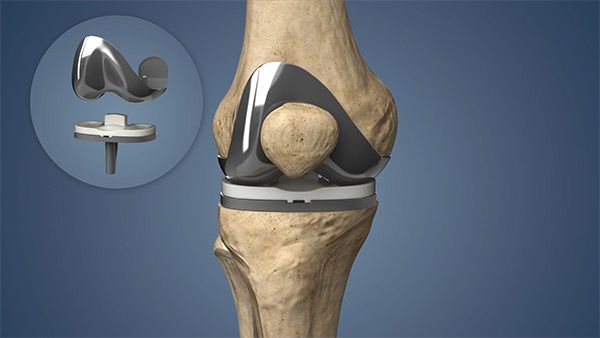

Joint Care & Replacement

Expert evaluation and surgical management of arthritis and joint disorders, including total knee replacement, Robotic knee resurfacing surgery, partial knee replacement and hip replacement.